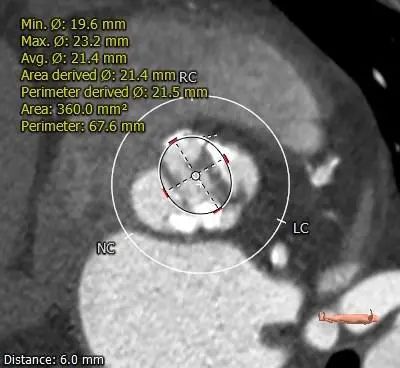

Type 0型二叶式主动脉瓣,重度钙化,无冠窦瓣叶边缘靠近左冠侧钙化较重呈团块状,钙化向对合边缘及流出道延伸,前窦钙化分布于窦内,瓣叶不规则增厚粘连。

冠脉开口高度可,左冠切线角度测量瓣叶略长于LCA开口下缘到根部距离。

瓦氏窦内径可,窦管交界、升主动脉内径可。

主动脉瓣环水平夹角61度,横位心,主动脉弓宽度、角度可。

根部影像非收缩期时相(Phase 71%)。

ANNULUS